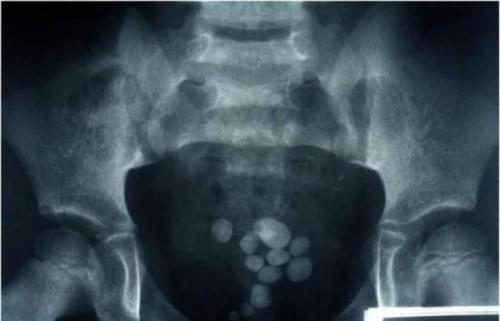

Иоанн Летейский — удаление камня из мочевого пузыря

О нем стало известно из книги голландского доктора Николаса Тульпа, жившего в 17 веке. Тульп был мэром Амстердама.

Камень, к слову, был размером с куриное яйцо. При операции присутствовал только его брат. Иоанн сделал надрез в промежности, зажав камень левой рукой, и вытащил его. Но для того, чтобы наложить швы, кузнец все-таки пригласил врачей.